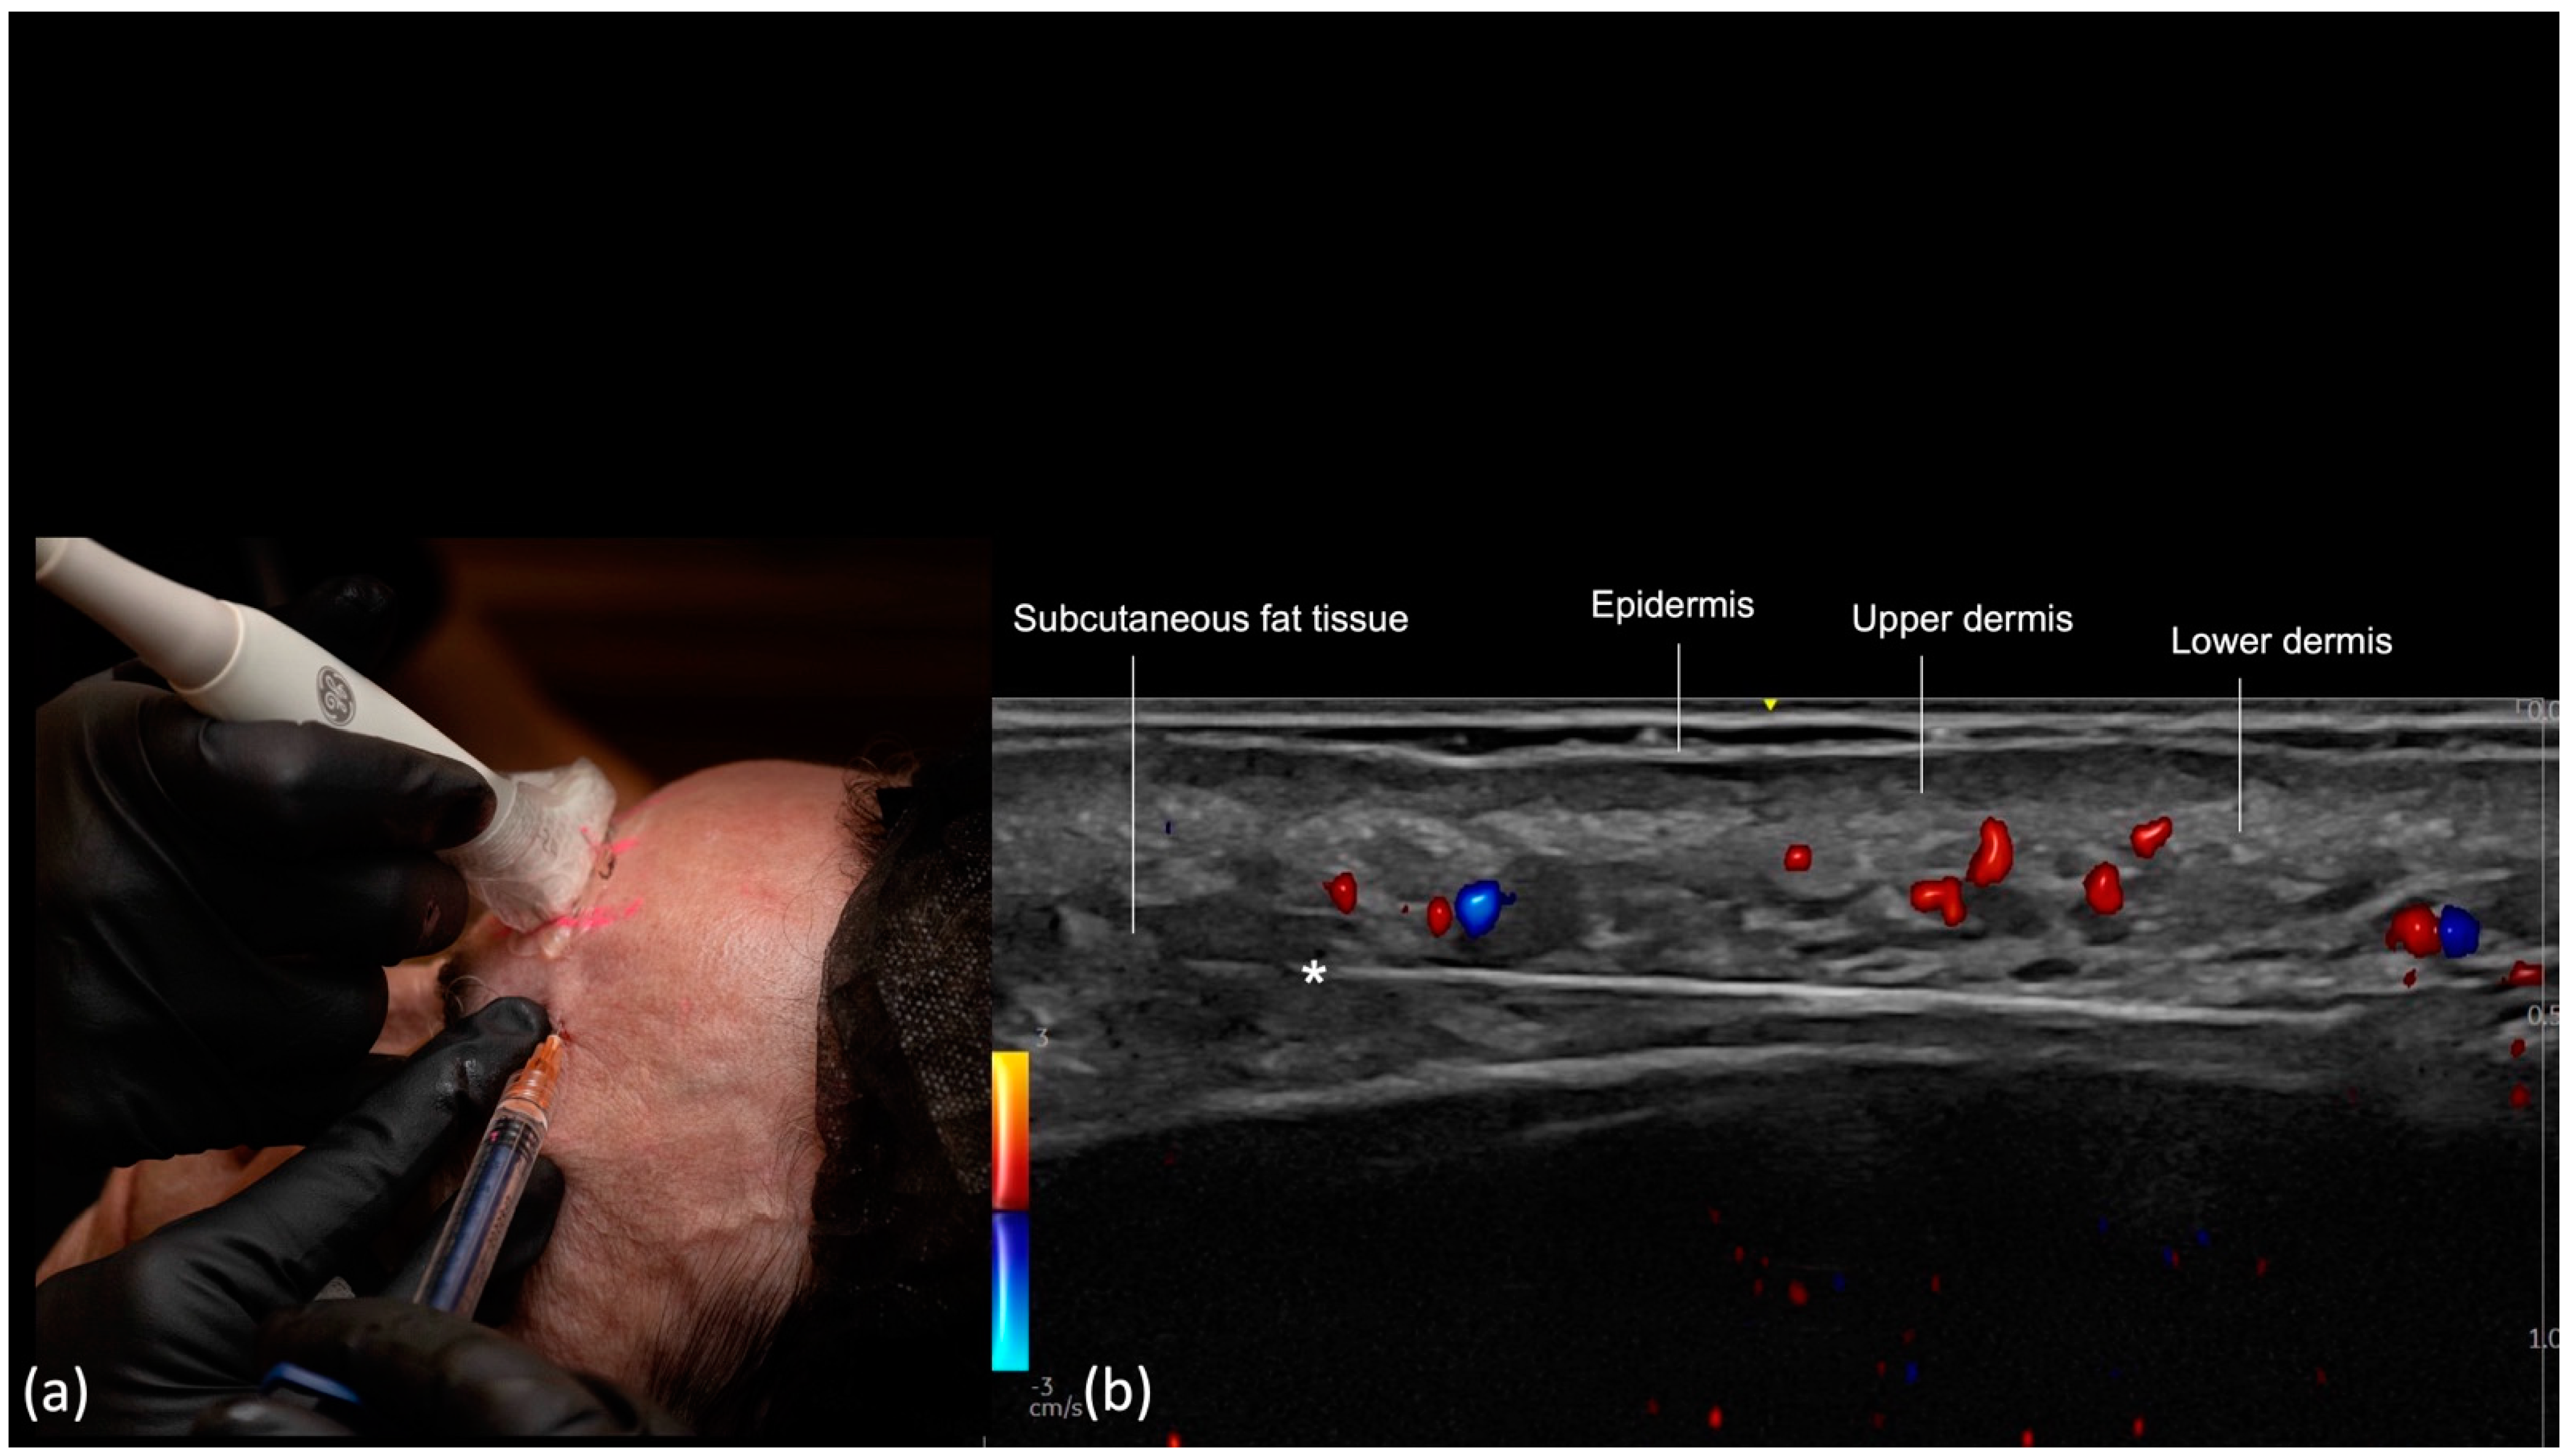

Glabella

- Scan before injecting: The treatment area is scanned immediately before injection to assess the presence of vessels. The trajectory of the main arteries might be marked on the patient’s skin.

- Scan while injecting: In this case, the cannula is visualized in real time and positioned in the desired anatomical region, avoiding vascular structures.

| Frontal Region: Glabella | Yes | Yes | Usually superficial, may vary according to the depth of the arteries on DUS | Supratrochlear, central and paracentral arteries |